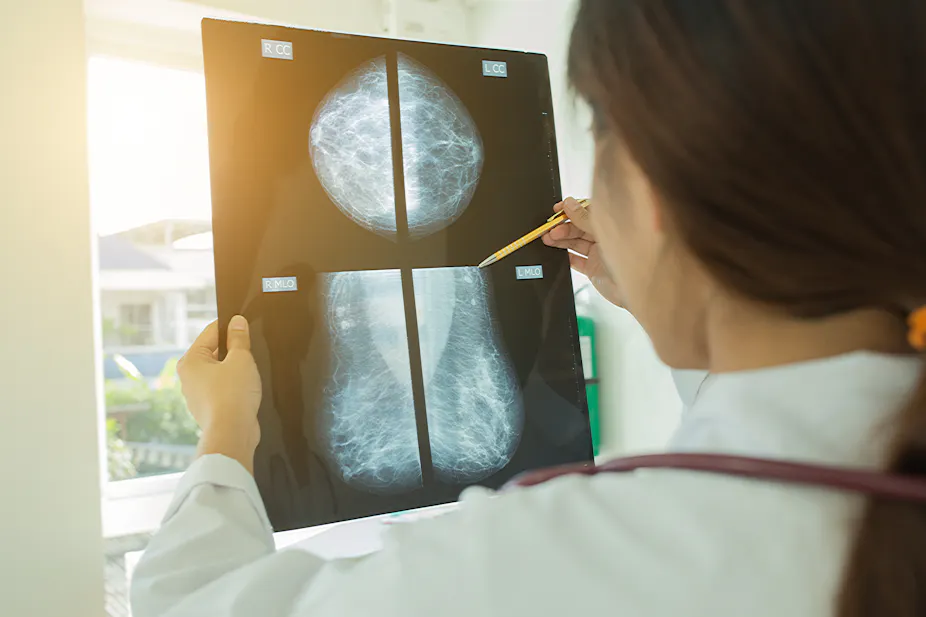

For breast cancer, the focus so far has been on how AI can help diagnose the disease from mammograms. Every mammogram is read by two specialists, which can lead to potential delays in diagnosis if there is a shortfall in expertise. But researchers have been looking at introducing AI systems at the time of the screening. The idea is that it would support a specialist’s findings without waiting for the second opinion of another professional. This would reduce the waiting time and associated anxiety for the women who have been tested.

AI has already made substantial strides in cancer image recognition. In late 2018, researchers reported that one commercial system matched the accuracy of over 28,000 interpretations of screening mammograms by 101 radiologists. This means it achieved a cancer detection accuracy comparable to an expert radiologist.

In another study led by the same researcher, radiologists using an AI system for support showed an improved rate of improved breast cancer detection – rising from 83% to 86%. This research also found that using an AI system reduced the amount of time radiologists spent analysing the images on screen.